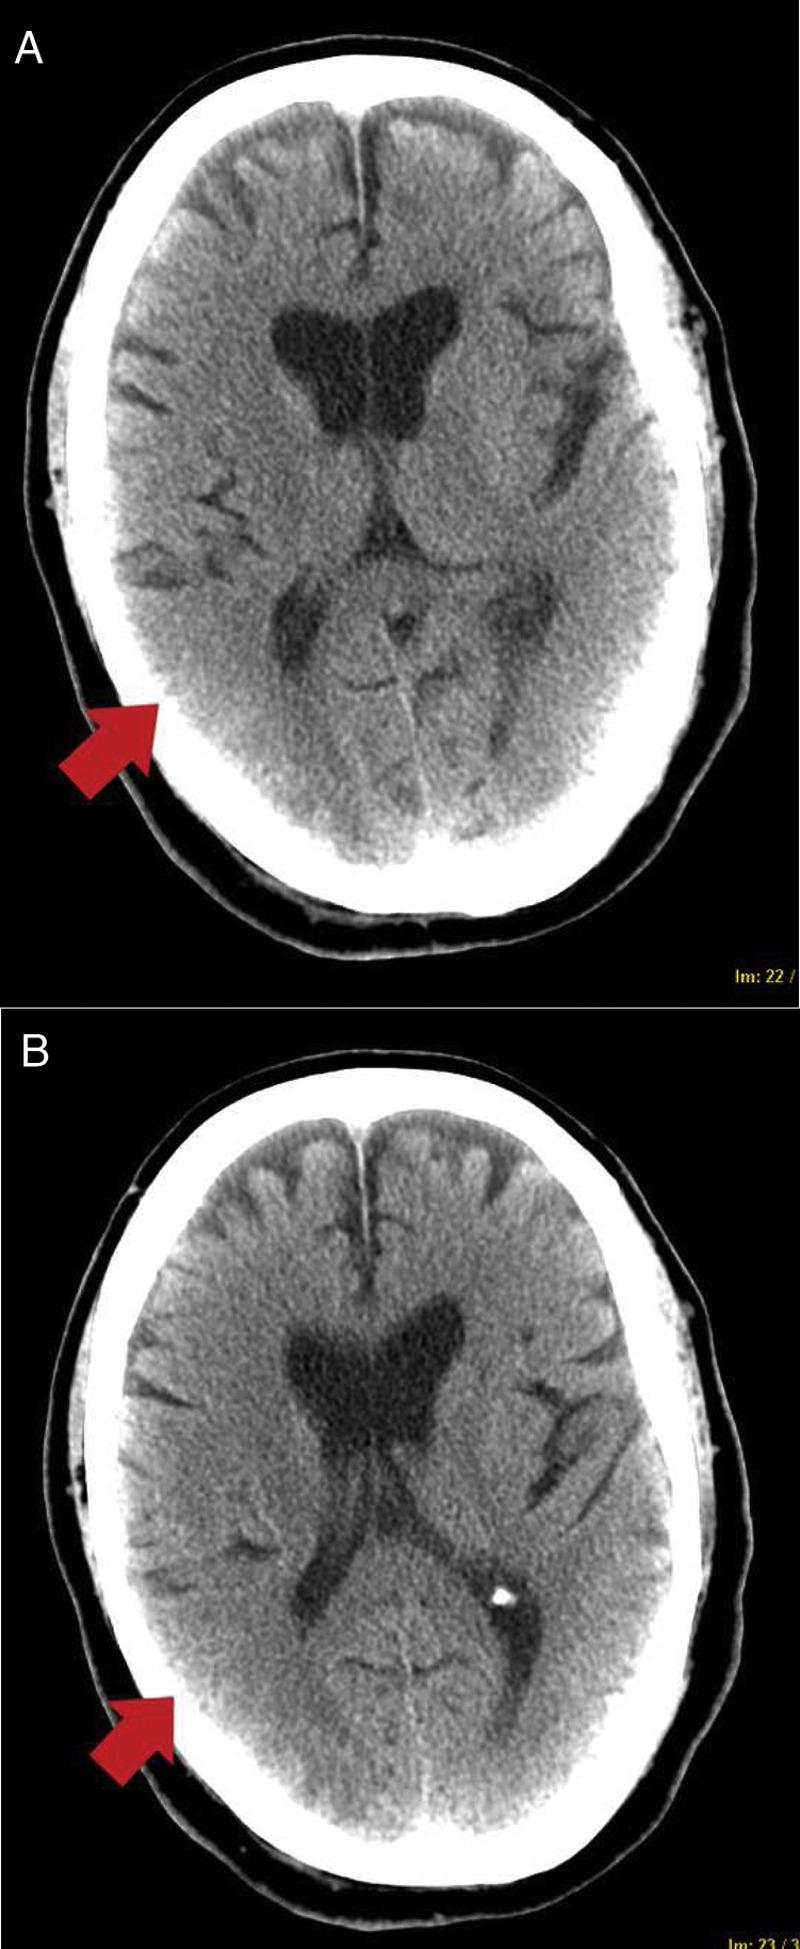

Posterior reversible encephalopathy syndrome is an acute neurological disorder characterized by variable symptoms and radiological images characteristic of vasogenic parietal-occipital edema. It is associated with clinical conditions such as high blood pressure, infection/sepsis, or cytotoxic/immunosuppressive drugs, among others. It is characterized pathophysiologically by endothelial damage with breakdown of blood-brain barrier, cerebral hypoperfusion, and vasogenic edema. The cases are presented on 2 critical COVID-19 patients who were admitted to pneumonia requiring mechanical ventilation and who, after removing sedation, developed acute and reversible neurological symptoms consisting of epilepsy and encephalopathy, associated with hyperintense subcortical lesions on brain magnetic resonance imaging compatible with posterior reversible encephalopathy syndrome. SARS-CoV-2 coronavirus would activate an inflammatory response that would damage brain endothelium. It could be triggered by cytokine release, as well as by direct viral injury, given that endothelium expresses ACE2 receptors. It could explain the possible association between posterior reversible encephalopathy syndrome and COVID-19.